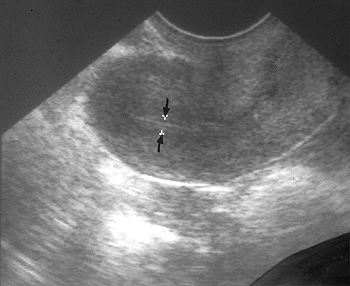

동결란 이식에서 자궁내막의 두께의 중요성 : 호르몬 보충법과 자연주기 동결란 이식법 사이에서 차이점

2012년 미국불임학회 (ASRM) P-51

동결란 이식에서 자궁내막의 두께의 중요성 : 호르몬 보충법과 자연주기 동결란 이식법 사이에서 차이점